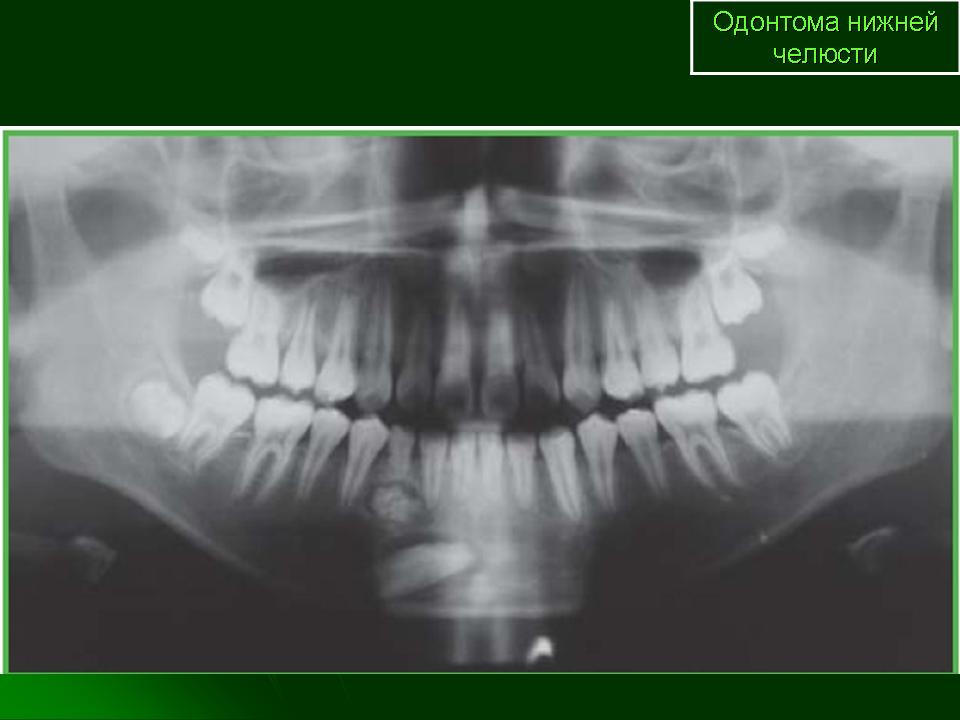

Одонтома - опухоль, образующаяся в результате порока развития и формирования зубных тканей. Одонтомы разделяются на простые и сложные. Простая одонтома связана с пороком развития одного зубного зачатка. Сложная одонтома связана с нарушением развития нескольких зачатков зубов, поэтому содержит твердые ткани на разных стадиях развития. В редких случаях одонтома имеет вид кисты, содержащей почти сформированные зубы. При гистологическом исследовании опухоли обнаруживают различные ткани: эмаль, дентин, цемент, пульпу, фиброзную ткань, кость. В мягких (кистоподобных) одонтомах в стенках содержатся зачатки элементов зубного эпителия. Одонтомы чаще встречаются в молодом возрасте. Растут медленно. Локализуются в основном в нижней челюсти. Рентгенологическая диагностика одонтом не представляет особых трудностей. На фоне обычной костной ткани выявляется очень плотное, округлой формы образование, окруженное ободком просветления (за счет фиброзной капсулы). В зубном ряду, как правило, отсутствует один или несколько зубов.

Одонтома